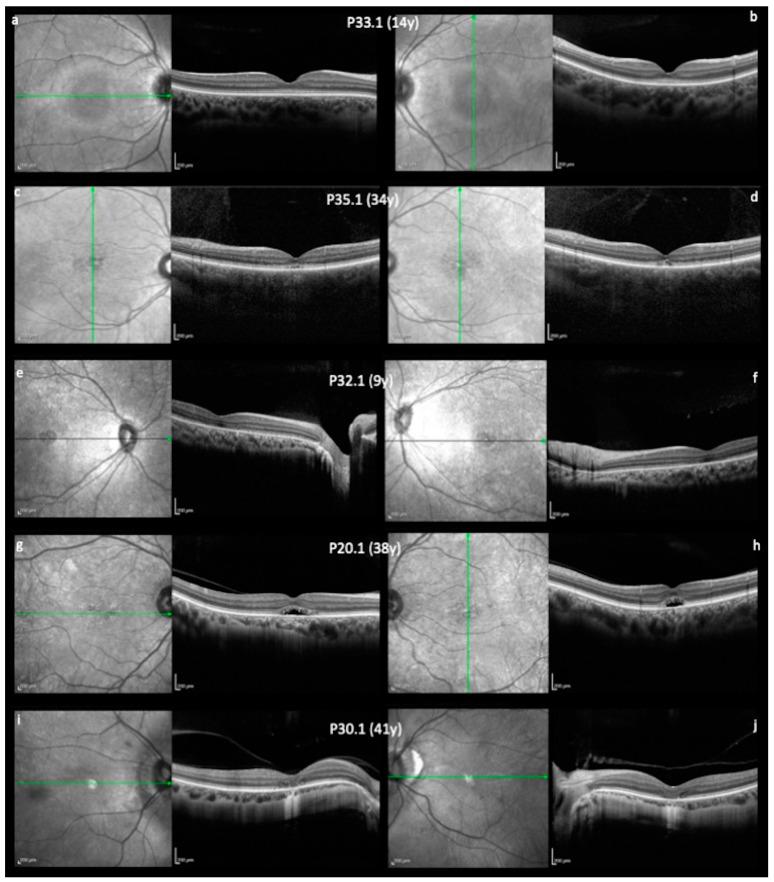

Achromatopsia (ACHM) is a congenital cone photoreceptor disorder characterized by reduced visual acuity, nystagmus, photophobia, and very poor or absent color vision. Pathogenic variants in six genes encoding proteins composing the cone phototransduction cascade (, , , , ) and of the unfolded protein response () have been related to ACHM cases, while and alone are responsible for most cases. Herein, we provide a clinical and molecular overview of 42 Brazilian patients from 38 families affected with ACHM related to biallelic pathogenic variants in the and genes. Patients' genotype and phenotype were retrospectively evaluated. The majority of variants were missense, and the most prevalent variant was c.1148delC (p.Thr383Ilefs13), resulting in a frameshift and premature stop codon, which is compatible with previous publications in the literature. A novel variant c.1893T>A (p.Tyr631) in the gene is reported for the first time in this study. A great variability in morphologic findings was observed in our patients, although no consistent correlation with age and disease stage in OCT foveal morphology was found. The better understanding of the genetic variants landscape in the Brazilian population will help in the diagnosis of this disease.

全色盲(ACHM)是一种先天性的 Cone 光感受器疾病,其特征为视力下降、眼球震颤、畏光以及非常差或完全丧失色觉。与 ACHM 病例相关的致病性变异存在于六个编码 Cone 光转导级联蛋白的基因(,,,,, )和未折叠蛋白反应(UPR)中,而 和 单独负责大多数病例。在此,我们对 38 个家系的 42 名巴西 ACHM 患者进行了临床和分子概述,这些患者均与 和 基因的双等位基因致病性变异相关。我们回顾性评估了患者的基因型和表型。大多数 变异为错义突变,最常见的 变异是 c.1148delC(p.Thr383Ilefs13),导致移码和提前终止密码子,这与文献中的先前报道一致。我们首次在该研究中报道了 基因中的新型变异 c.1893T>A(p.Tyr631)。我们的患者在形态学发现方面存在很大的变异性,尽管在 OCT 黄斑形态中未发现与年龄和疾病阶段的一致相关性。更好地了解巴西人群中的遗传变异景观将有助于该疾病的诊断。